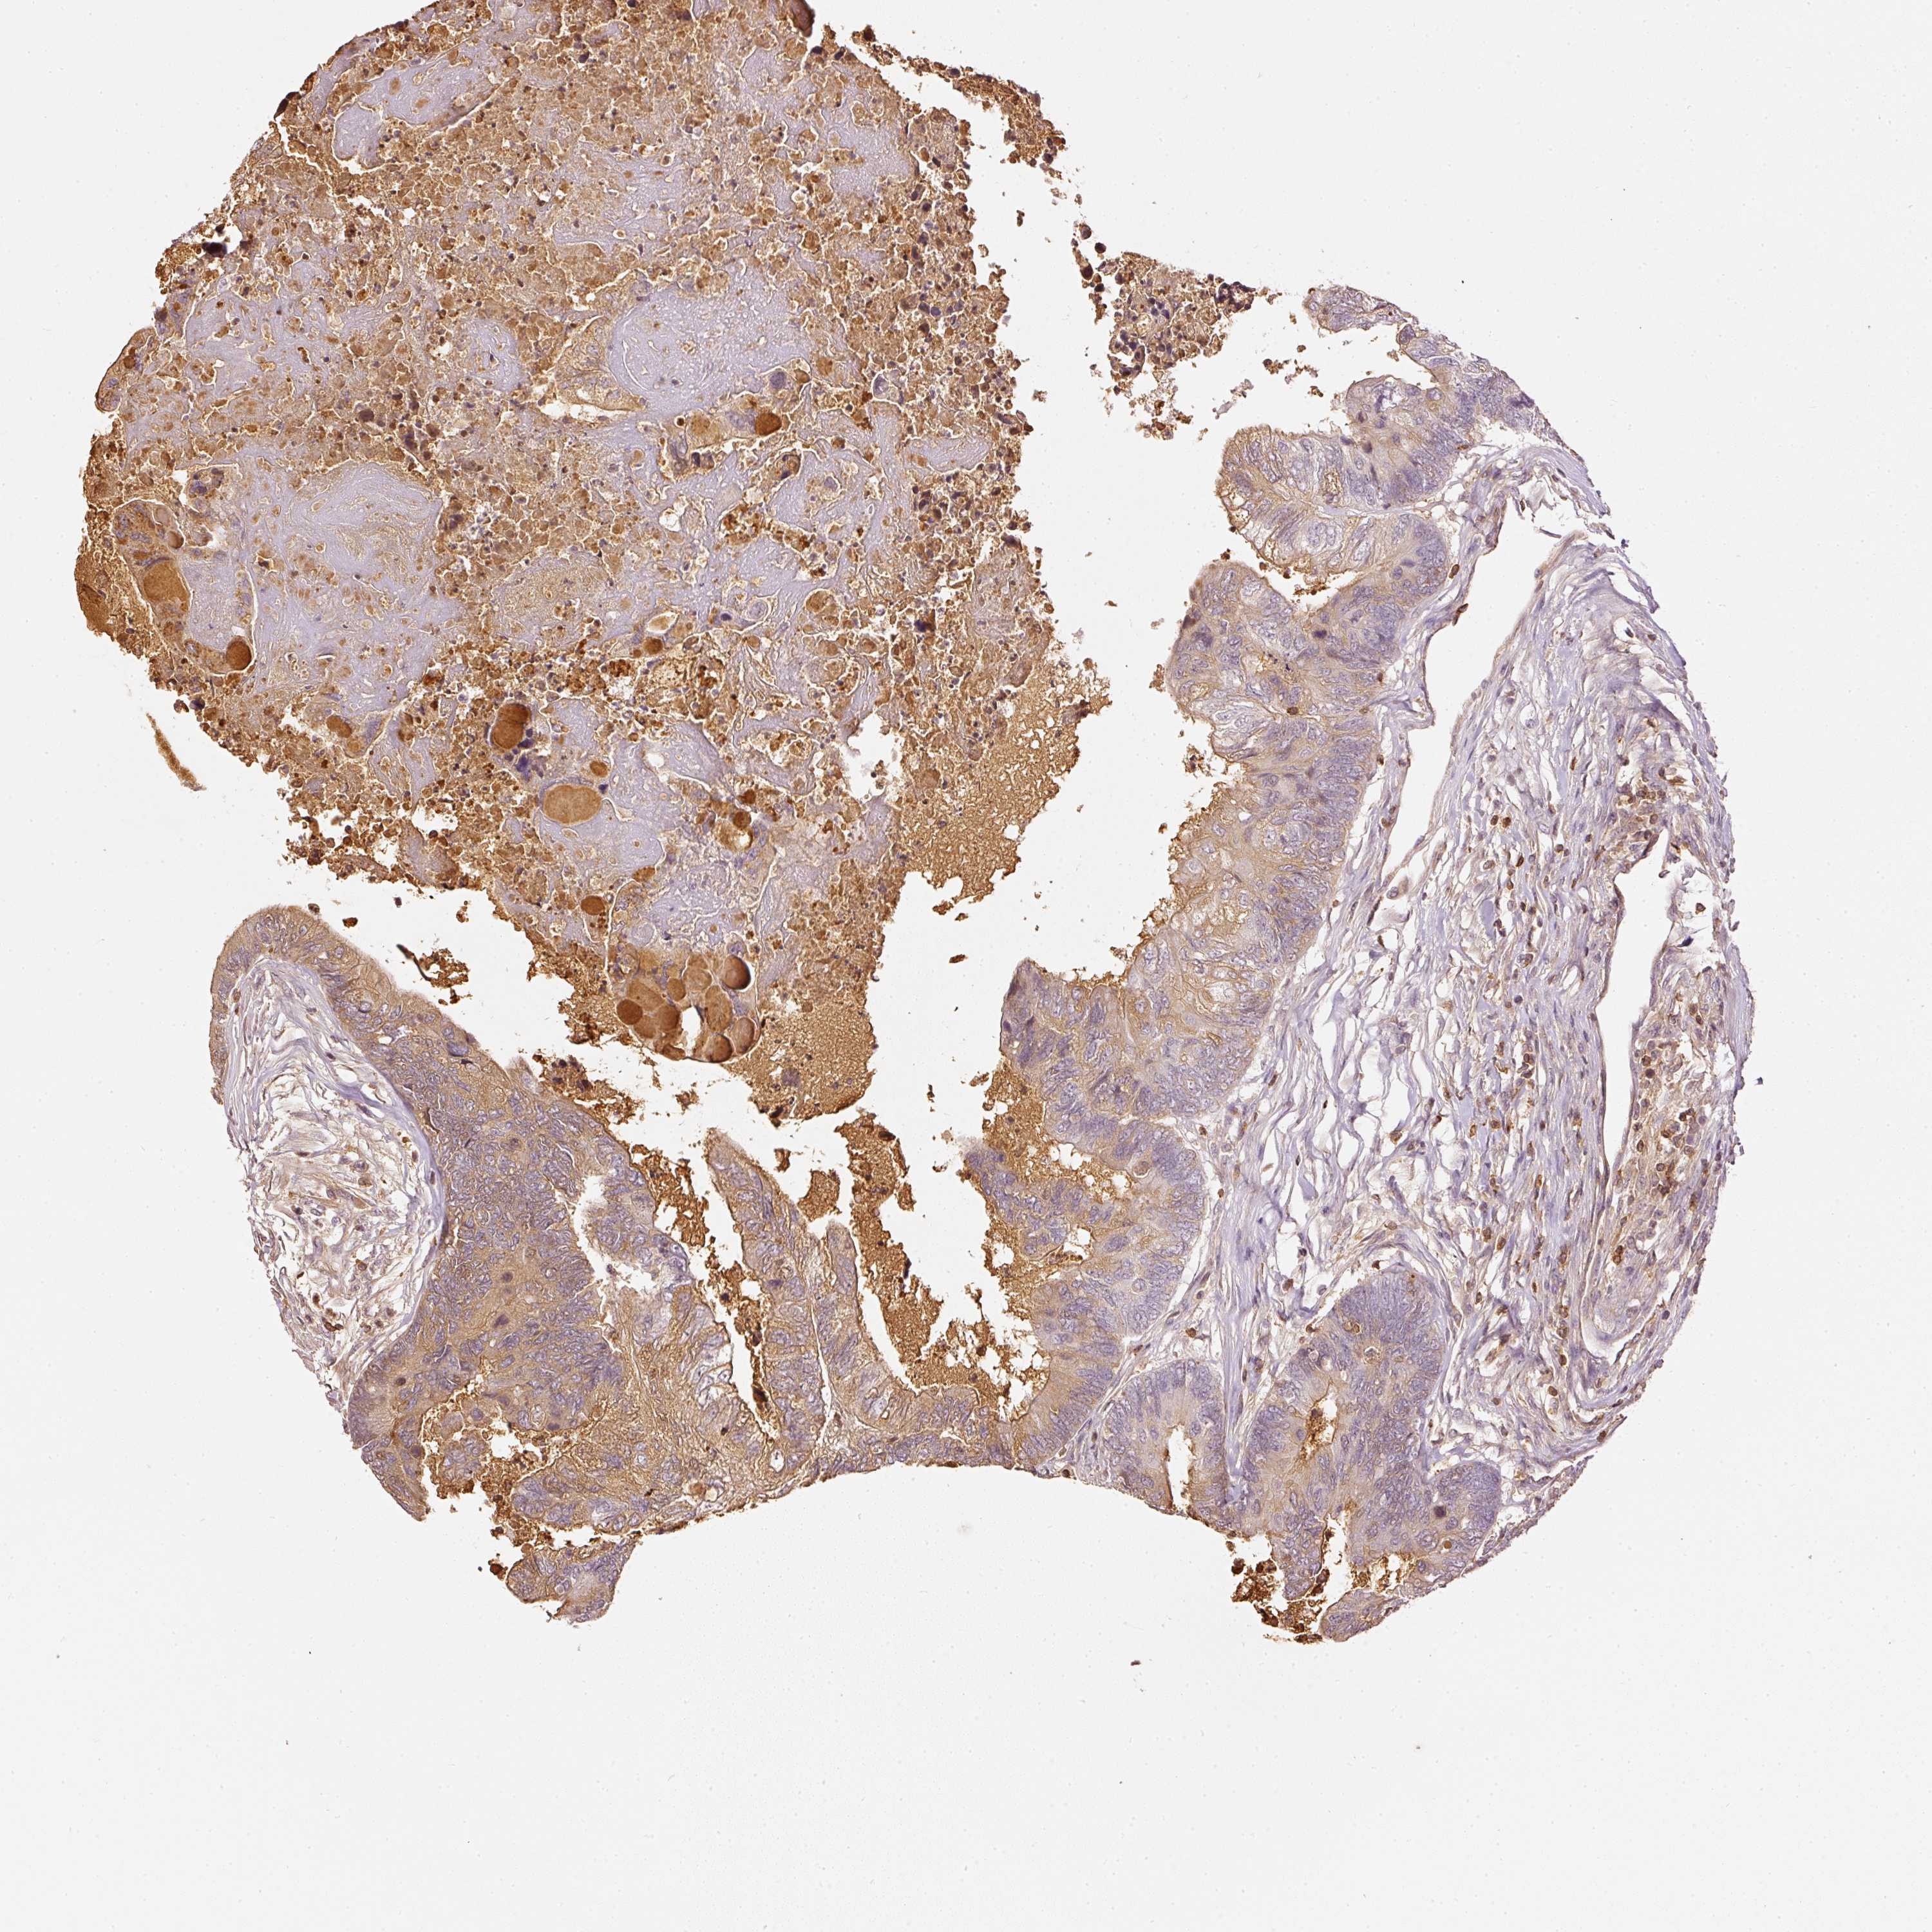

CANCER COLORECTAL CANCER Show tissue menu

COAD TCGA COAD VALIDATION READ TCGA READ VALIDATION PROTEIN COAD CPTAC PROTEIN EXPRESSION

ANTIBODIES

AND

VALIDATION